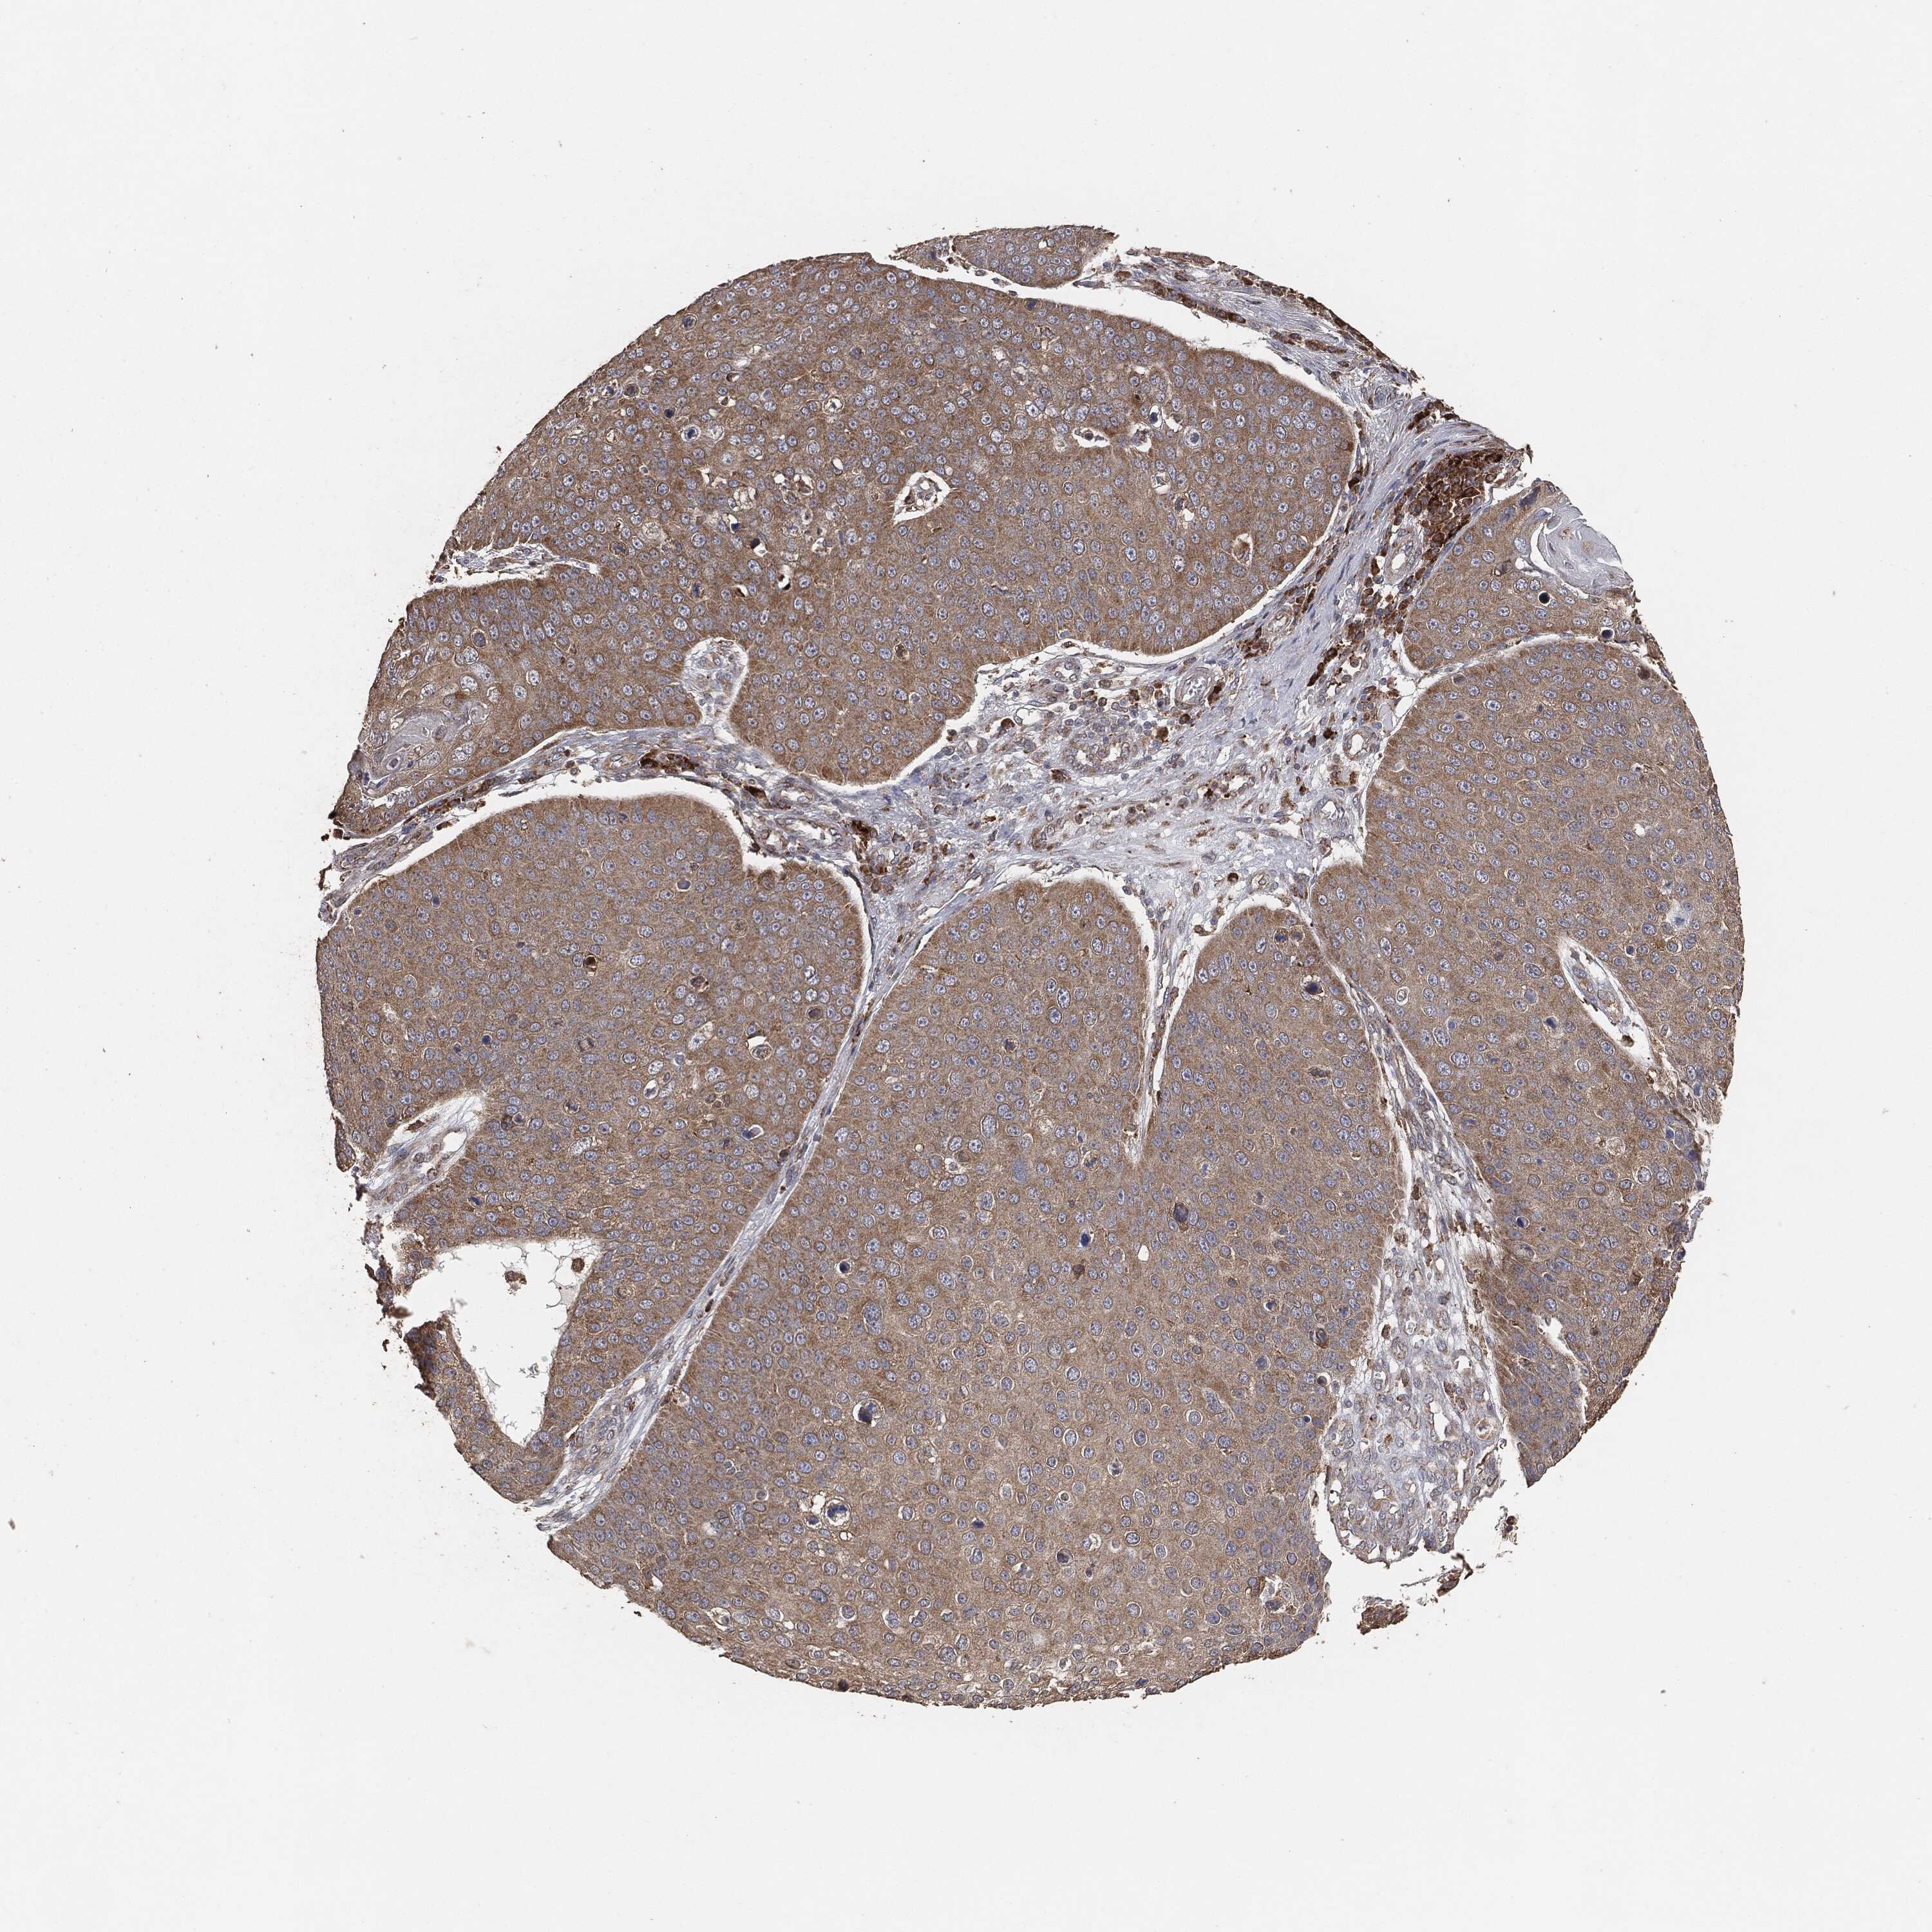

SKIN CANCER - Protein expressioni

A mouse-over function shows sample information and annotation data. Click on an image to view it in a full screen mode. Samples can be filtered based on level of antibody staining by selecting one or several of the following categories: high, medium, low and not detected. The assay and annotation is described here.

Antibody staining in the annotated cell types in the current human tissue is reported as not detected, low, medium, or high, based on conventional immunohistochemistry profiling in selected tissues. This score is based on the combination of the staining intensity and fraction of stained cells.

Each image is clickable and will lead to virtual microscopy that enables deeper exploration of all samples and also displays staining intensity scores, fraction scores and subcellular localization as well as patient and tissue information for each sample.

Squamous cell carcinoma, NOS

Basal cell carcinoma

Squamous cell carcinoma in situ, NOS

Squamous cell carcinoma, metastatic, NOS